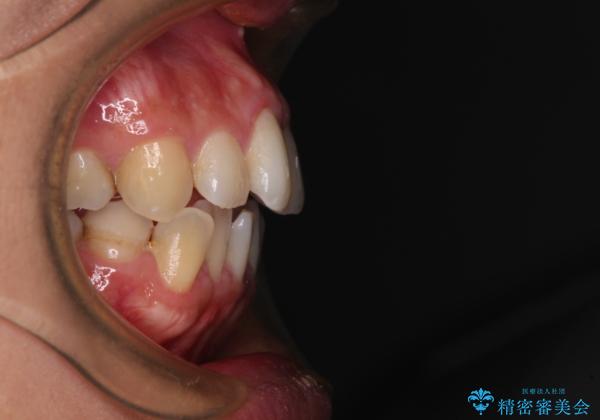

- 前歯のデコボコを治したいとのことで来院された患者様です。

上下顎ともに歯列全体の後方移動とIPR(歯と歯の間を削る)によってデコボコが解消するように設計し、インビザラインにより治療を行うこととしました。